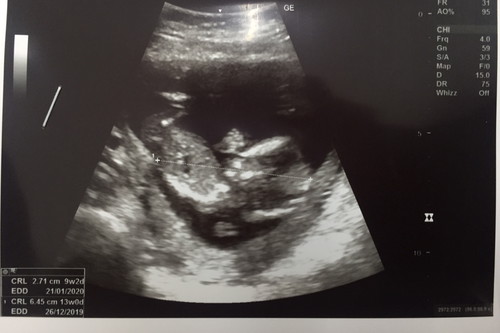

อยากเห็นภาพ13สัปดาห์ ของแม่ท่านอื่นจังเลยค่ะ

ใครชำนาญพอมองเพศออกบ้างคะ

ขอโทษนะคะ ภาพนี้พอดูออกไหมคะ ว่าเพศอะไร

ต้องถ่ายใต้ขาคะ นี่ลำตัว ดูไม่ออกคะ

ภาพตอนตอน 13+1 W ค่ะ ตอนนี้ 16+1 W ละค่ะ